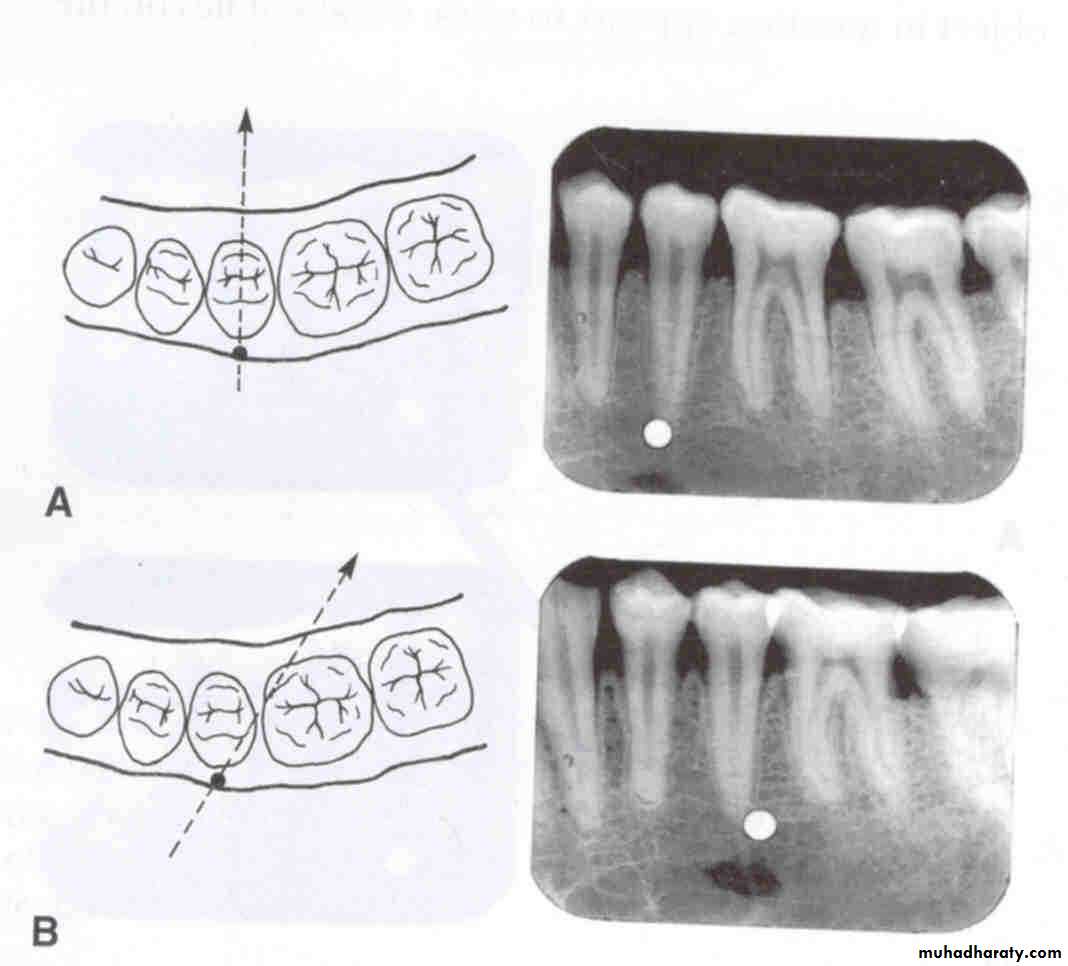

Vertical movement of the tubehead and x-ray beam

In moving from the maxillary periapical to the bitewing and from the bitewing to the mandibular periapical, the tube head moves down and the beam is redirected upward (opposite direction; decreased vertical angulation).

In the diagram at left, the buccal (yellow) and lingual (red) objects of interest are superimposed on each other because the beam is directed perpendicular to both of them and they are in the same relative position mesiodistally and vertically. Both images are superimposed over the mandibular second premolar.

Vertical movement

In the diagram at left, the tube head is moved upward and the beam is directed downward. On the radiograph, the buccal object of interest (yellow) moves down (opposite to tube head movement) in relation to the second premolar and the lingual object of interest (red) moves up (same direction as tube head) in relation to the second premolar.

In the diagram at left, the tube head is moved downward and the beam is directed upward. On the radiograph, the buccal object of interest (yellow) moves up (opposite to tube head movement) in relation to the second premolar and the lingual object of interest (red) moves down (same direction as tube head) in relation to the second premolar.